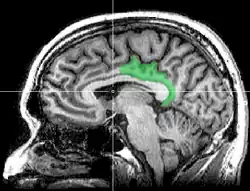

![]() Sagittal MRI slice with highlighting indicating location of the posterior cingulate | |

The posterior cingulate cortex (PCC) is the caudal part of the cingulate cortex, located posterior to the anterior cingulate cortex. This is the upper part of the "limbic lobe". The cingulate cortex is made up of an area around the midline of the brain. Surrounding areas include the retrosplenial cortex and the precuneus.

The posterior cingulate cortex lies behind the anterior cingulate cortex, forming a part of the posteromedial cortex, along with the retrosplenial cortex (Brodmann areas 29 and 30) and precuneus (located posterior and superior to the PCC). The PCC, together with the retrosplenial cortex, forms the retrosplenial gyrus. The posterior cingulate cortex is bordered by the following brain regions: the marginal ramus of the cingulate sulcus (superiorly), the corpus callosum (inferiorly), the parieto-occipital sulcus (posteriorly), and Brodmann area 24 (anteriorly).[4]